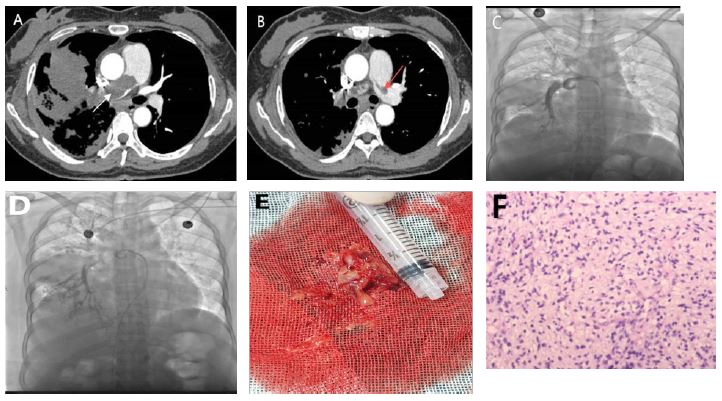

Over two months ago, the patient started coughing without an obvious cause, along with producing a small amount of white mucoid sputum and experiencing right-sided chest pain. A chest CT scan at a local hospital showed a 3.2 cm patchy shadow in the middle lobe of the right lung, along with pleural effusion. A percutaneous lung biopsy indicated a potential diagnosis of tuberculosis. She was diagnosed with secondary pulmonary tuberculosis and treated with the HRZE regimen for four weeks; however, her symptoms did not improve, and she developed new-onset dyspnea. A pulmonary artery CTA revealed a filling defect in the trunk of the right pulmonary artery, indicating a potential pulmonary embolism (Figure 1A & 1B).

The patient received interventional surgery on the pulmonary artery, followed by an endovascular biopsy guided by DSA, which collected fleshy tissue (Figure 1C, 1D, & 1E). The pathology report showed the following immunohistochemical results: Vimentin positive, focal smooth muscle actin positive, partial Desmin positive, and negative for S100, SOX-10, SS18-SSX, Myogenin, cytokeratin, CD34, STAT6, and EMA. Ki67 was greater than 80%. The pathological diagnosis was a spindle cell tumor of the pulmonary artery with necrosis, along with immunohistochemistry confirming intimal sarcoma (Figure 1F).

Figure 1: Imaging Diagnosis Process and Key Evidence for Pathological Diagnosis. (A) The maximum cross-sectional size of the shadow in the middle lobe of the right lung is approximately 85×73 mm, and a filling defect is visible in the main trunk of the right pulmonary artery (indicated by the arrow). (A & B) A filling defect is visible in the left pulmonary artery trunk (indicated by the arrow). (C & D) Pulmonary artery intervention surgery. (E) During the operation, tissue resembling fish meat and blood clots were extracted. (F) A spindle shaped multicell tumor with necrosis in the pulmonary artery, combined with immunohistochemistry, suggests arterial intimal sarcoma.